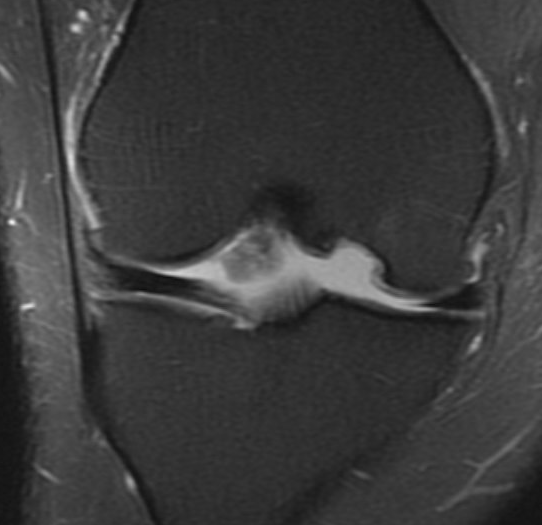

Chondral defect

Osteochondral defect